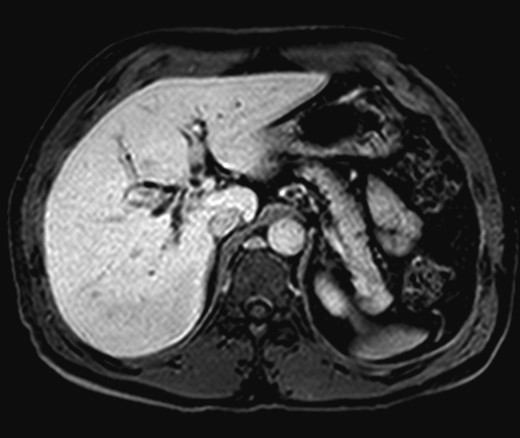

The patient is a 45-year-old African American male, previously healthy, but was examined at an outside facility for abdominal pain, jaundice, and abnormal liver function tests (LFTs) with hyperbilirubinemia. An esophagogastroduodenoscopy and endoscopic ultrasound was performed suggesting a dilated common hepatic duct to 1.4 cm with tapering of the duct at the ampulla to 6 mm, otherwise normal. Endoscopic retrograde cholangiopancreatography showed dilated intrahepatic right and left hepatic ducts with a tight hilar stricture, Bismuth Type I, with a 3 cm stricture encompassing the cystic and common bile ducts. Endoscopic brushings of the bile ducts showed benign glandular stromal tissue, non-diagnostic for malignancy. An MRI with contrast of the abdomen showed a non-cirrhotic liver with periductal thickening of the right and left central hepatic ducts with restricted diffusion and severe stenosis suggesting a Klatskin-type hilar cholangiocarcinoma, without evidence of extrahepatic disease (Figs 1 and 2). Imaging of the chest was negative for tumor. The laboratory workup showed normal liver function following endoscopic stenting, normal alpha-fetoprotein level, CA 19-9 and CEA. Colonoscopy was also negative for malignancy.

Preoperative MRI/MRCP with Bismuth Type I stricture of the common hepatic duct.

Preoperative axial T1 MRI with dilated right and left intrahepatic bile ducts.